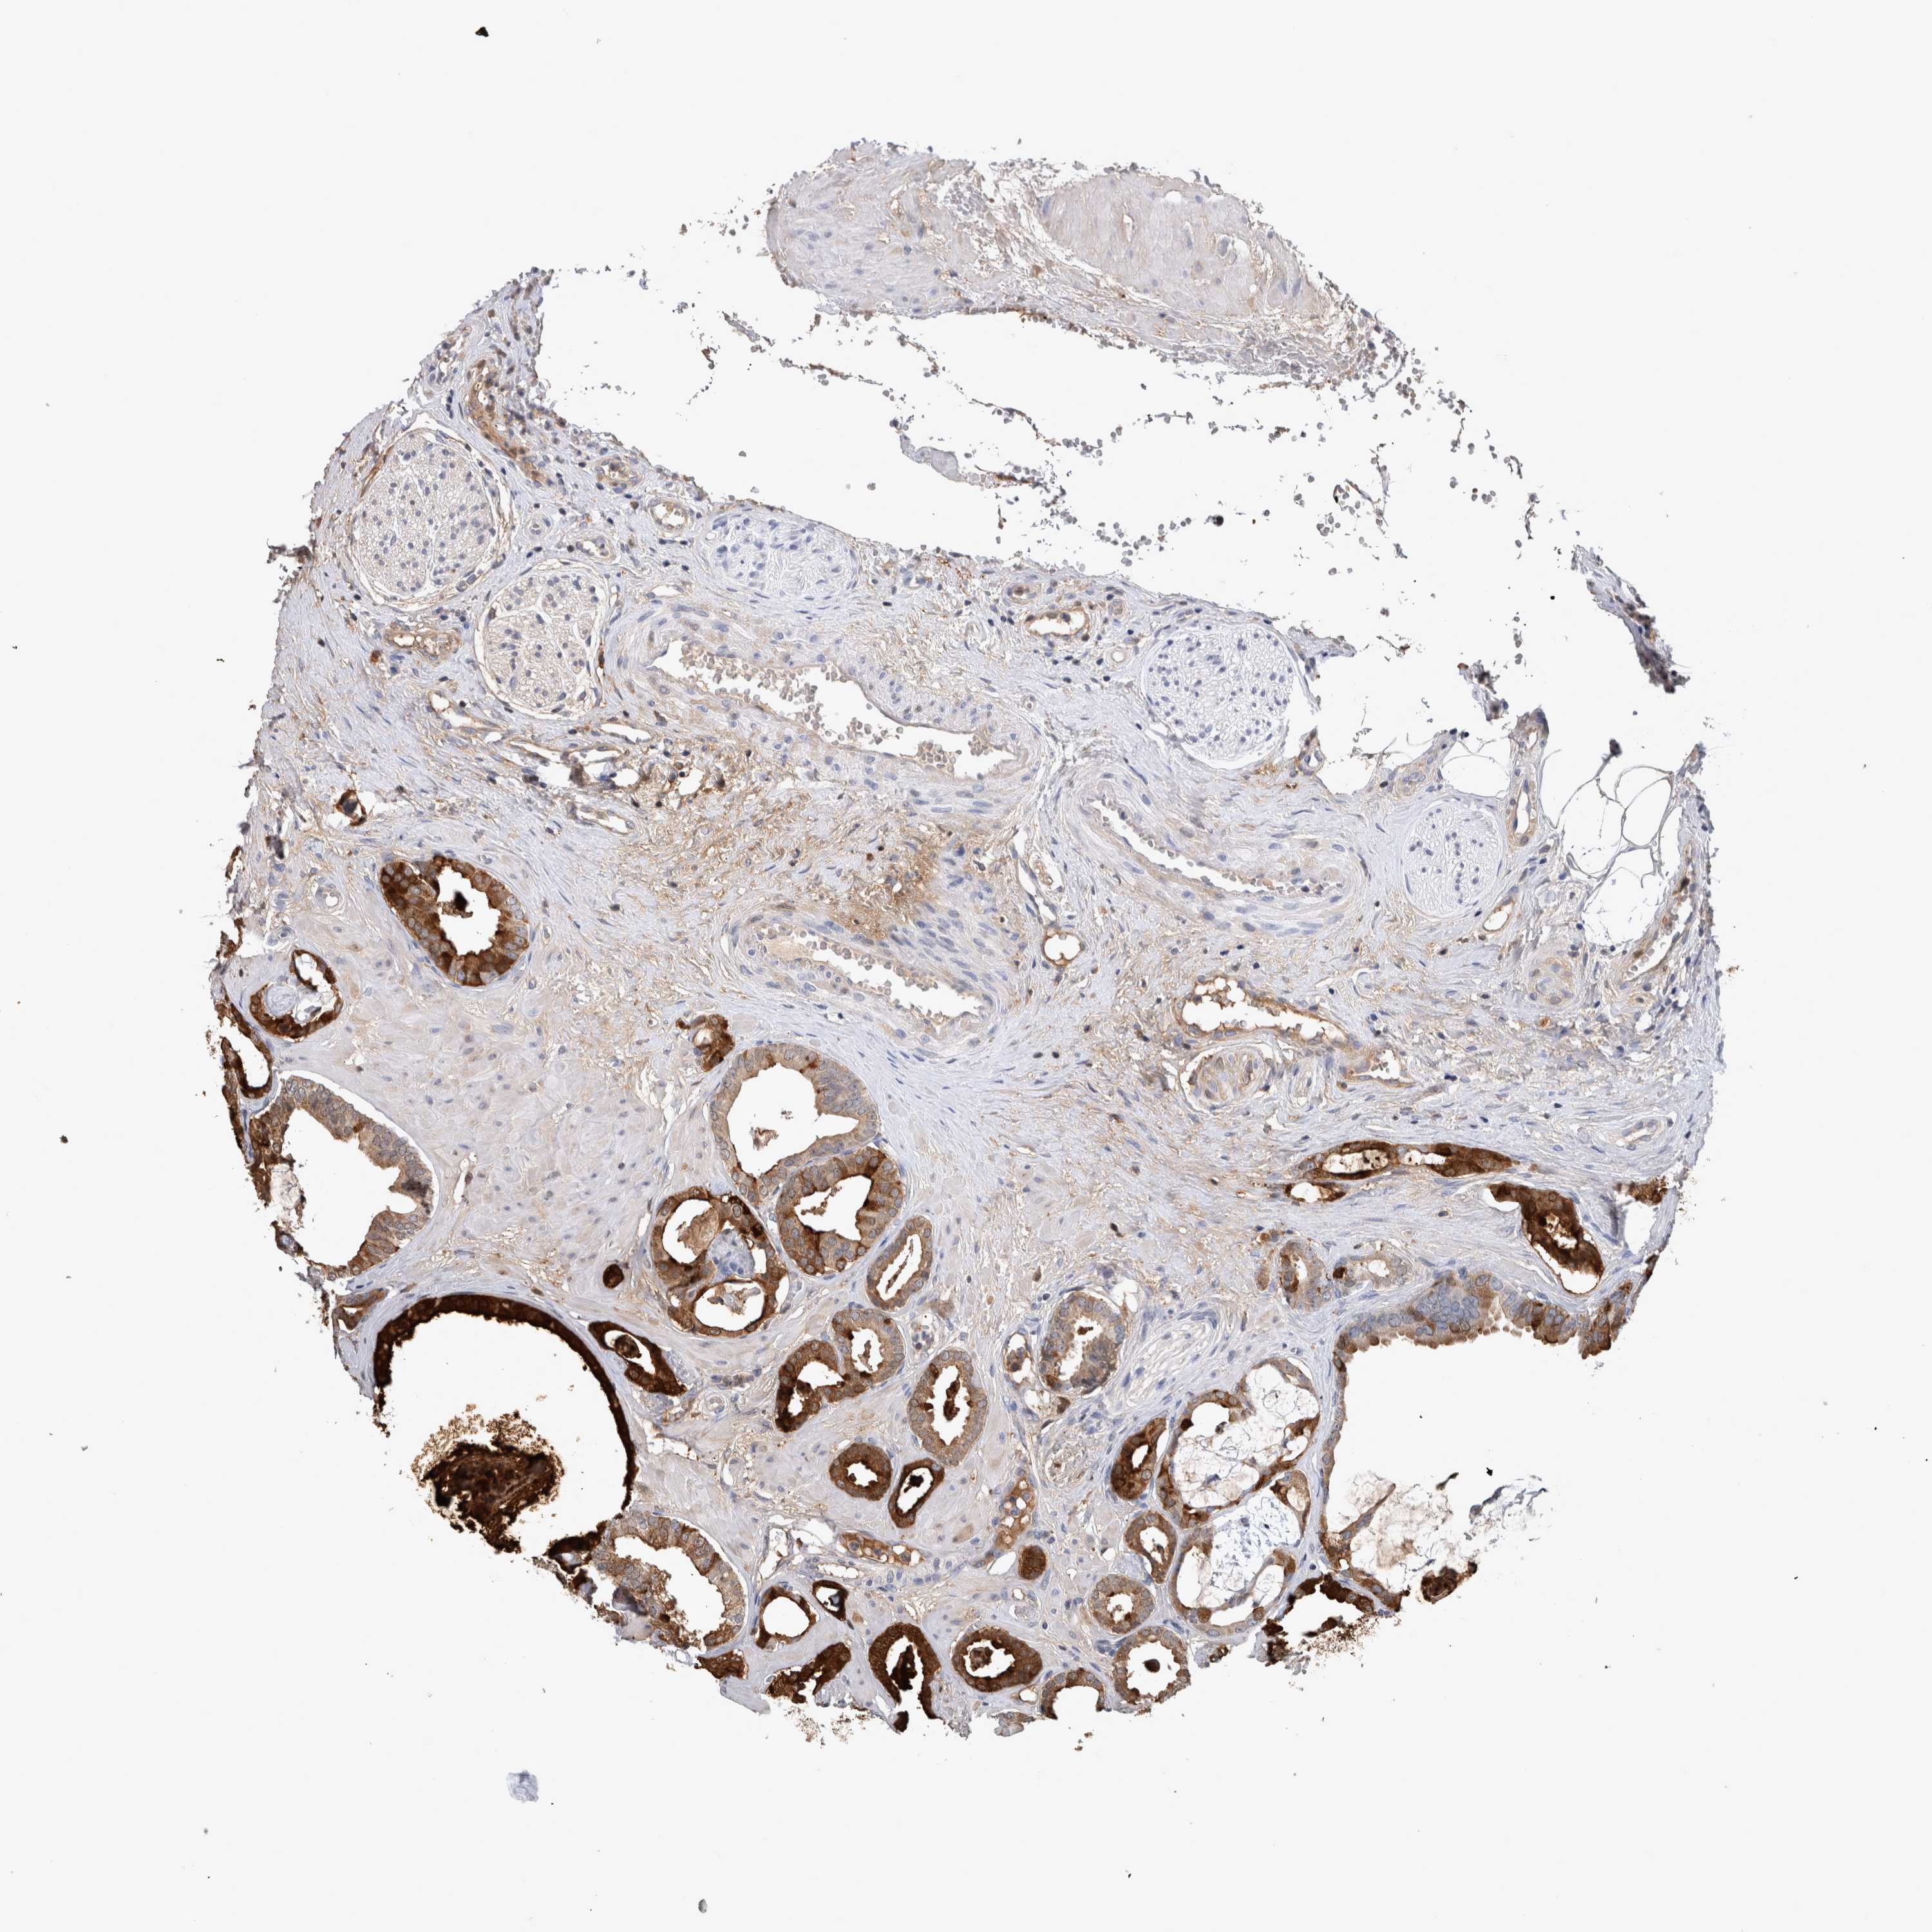

PROSTATE CANCER - Protein expressioni

A mouse-over function shows sample information and annotation data. Click on an image to view it in a full screen mode. Samples can be filtered based on level of antibody staining by selecting one or several of the following categories: high, medium, low and not detected. The assay and annotation is described here.

Antibody stainingi

Antibody staining in the annotated cell types in the current human tissue is reported as not detected, low, medium, or high, based on conventional immunohistochemistry profiling in selected tissues. This score is based on the combination of the staining intensity and fraction of stained cells.

Each image is clickable and will lead to virtual microscopy that enables deeper exploration of all samples and also displays staining intensity scores, fraction scores and subcellular localization as well as patient and tissue information for each sample.

Antibody HPA051257

Antibody CAB026357

Staining

High

Medium

Low

Not detected

Intensity

Strong

Moderate

Weak

Negative

Quantity

>75%

75%-25%

<25%

None

Location

Nuclear

Cytoplasmic/membranous

Cytoplasmic/membranous,nuclear

Adenocarcinoma, High grade

Adenocarcinoma, Medium grade

Adenocarcinoma, Low grade